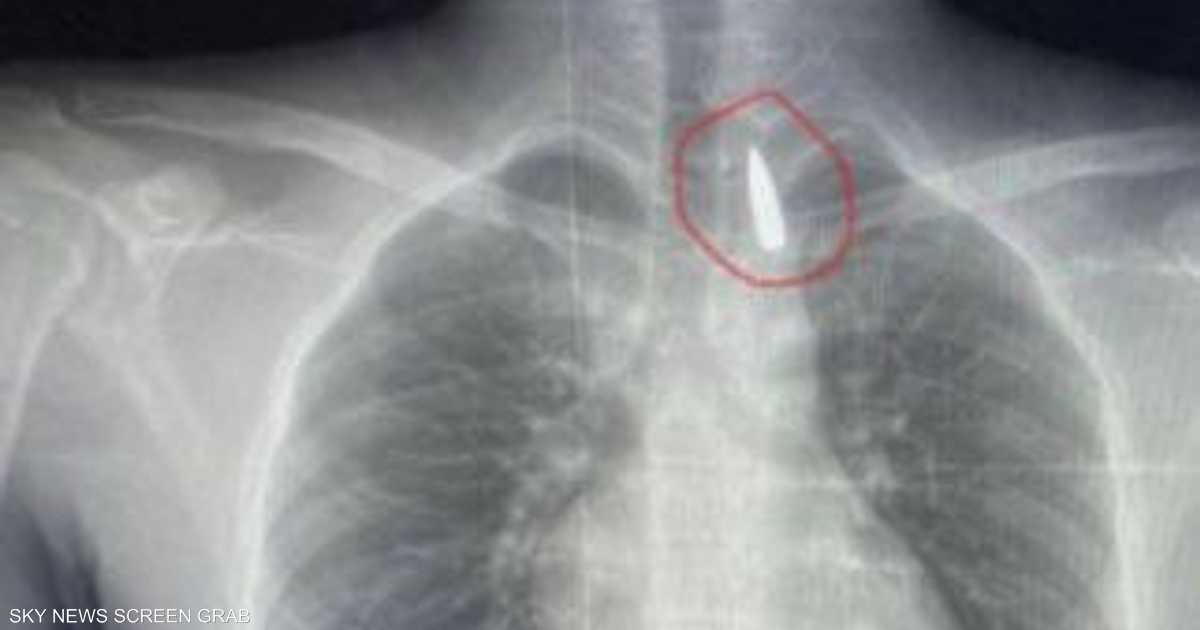

مقذوف استقر في صدره.. إنقاذ حياة مصاب من غزة في مصر

وأوضح عميد كلية الطب جامعة الإسكندرية ورئيس مجلس إدارة المستشفيات الجامعية تامر عبد الله، أن فريق من أطباء قسم جراحة القلب والصدر والتخدير والمعاونين تكمنوا من إجراء جراحة دقيقة بالغة الخطورة لأحد المرضى من قطاع غزة، والذي كان قد تعرض لإصابة بطلق ناري منذ فترة، استقر المقذوف على إثرها داخل تجويف القفص الصدري قرب الشريان الأورطي.

مبينا أن الفريق الطبي نجح، رغم دقة الحالة وتعقيدها، في استخراج المقذوف بأمان بعد عملية جراحية استمرت عدة ساعات داخل المستشفى الجامعي الجديد، حيث خضع المريض بعدها للرعاية الطبية اللازمة، مؤكدا أن حالة المريض حاليا مستقرة وتحت المتابعة الدقيقة من الفريق المختص.